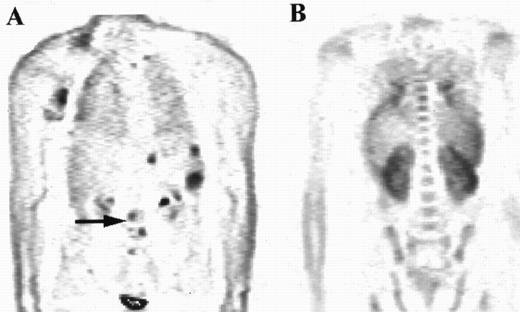

The distribution of uptake within the marrow was noted. Focal abnormality is seen within the lumbar spine in patient A (arrow), while patient B has diffuse marrow abnormalities.